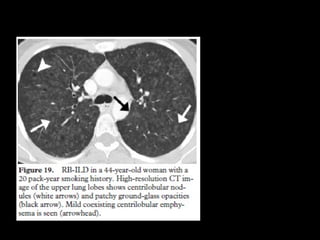

RB-ILD • RB Asintomático,hallazgo • Representan un continuo por la injuria del tabaquismo • Overlap • RB ILD se asocia más a fumadores • DIP: incluye drogas, polvo

CT • Nódulos centrolobularesLS • Vidrio esmerilado • Atrapamiento aéreo • Engrosamiento septal interlobular • DD: neumonitis por hipersensibilidad subaguda, DIP y NSIP

• Biopsia: bronbquiolitisacumulación intraluminal de macrófagos pigmentados